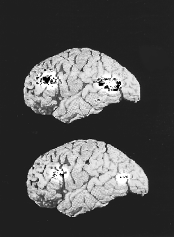

Два мозга были подвергнуты томографическому исследованию. На верхнем снимке - мозг, страдающий от депрессии, у него больший объем занимают затронутые болезнью участки (они отмечены бело-черными пятнами). На нижнем снимке - здоровый мозг.